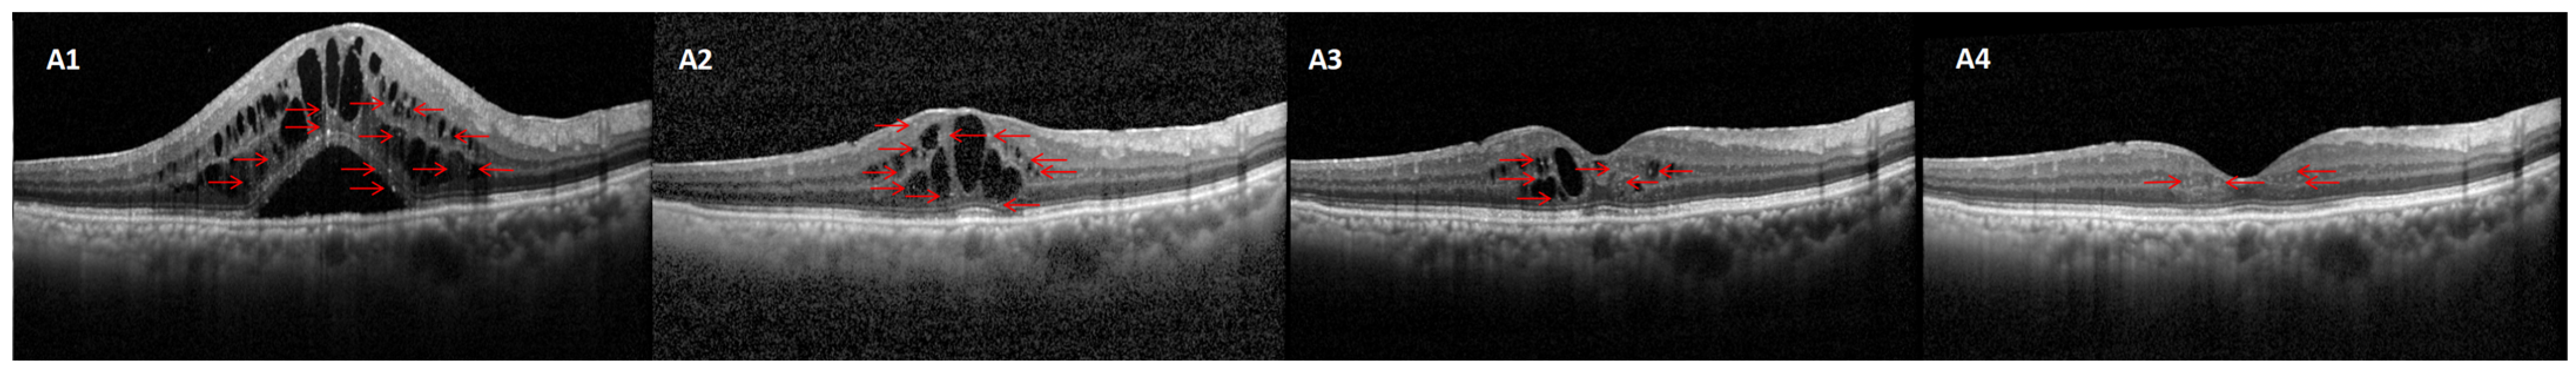

In this study, 112 eyes from 78 patients diagnosed with diabetic macular edema (DME) were included for analysis. Among these, 73 eyes (65%) demonstrated a positive response to ranibizumab treatment, as determined by predefined clinical criteria such as improved best-corrected visual acuity (BCVA) and reduced central retinal thickness (CRT) (Figure 1). In contrast, 39 eyes (35%) did not show a well-defined response, failing to meet these key improvement benchmarks. The 39 eyes that responded poorly to ranibizumab were subsequently treated with an intravitreal dexamethasone implant. Following this intervention, 26 eyes (66.67%) achieved a favorable outcome (Figure 2), while 13 eyes (33.33%) continued to exhibit a poor response to the treatment (Figure 3).

Figure 3. Example case of DME where dexamethasone treatment was ineffective. Baseline (C1) and post-IVR (C2C4) showing abundant HRDs (red arrow) with persistent CMT elevation (IVR non-responder). After receiving dexamethasone (C5), there is no noticeable decrease in CMT, although the quantity of HRD has diminished.